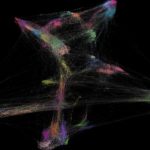

Study: Blue Brain solves a century-old neuroscience problem — (Details)

New research explains how the shapes of neurons can be classified using mathematical methods from the field of algebraic topology. Neuroscientists can now...